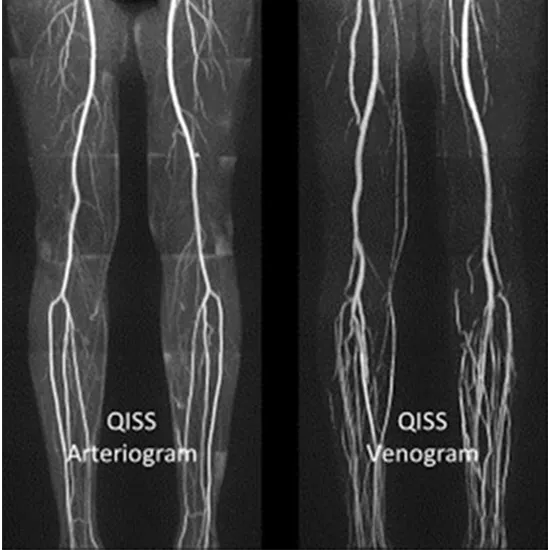

MRI Angiography Lower Limb is a scan that looks at the blood vessels (arteries and veins) bringing blood to the leg.